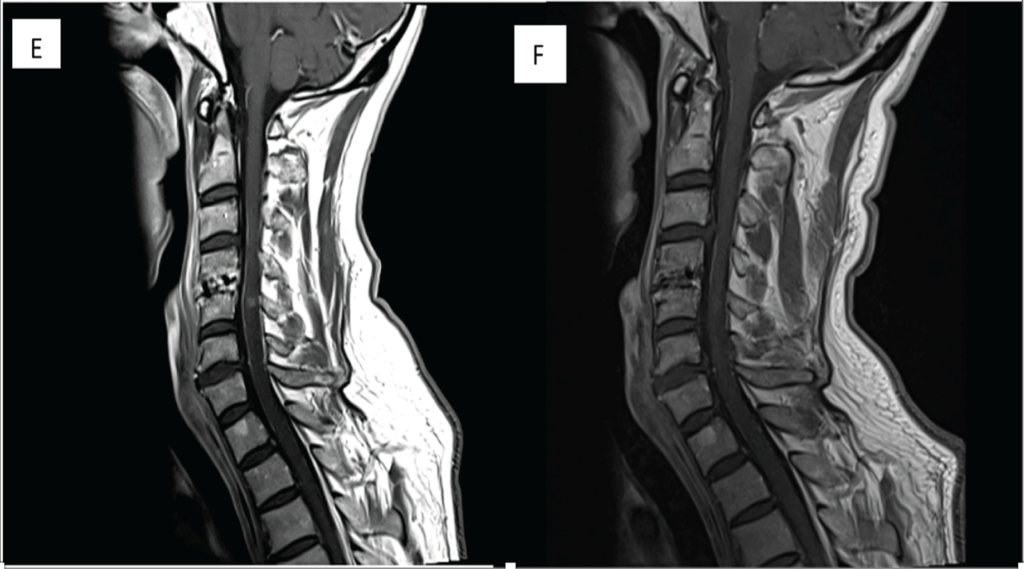

A sagittal T2-weighted magnetic resonance imaging of cervical spondylotic myelopathy patient shows the change of spinal cord signal intensity.